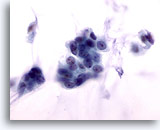

Figure 5

Breast FNA, Fibroadenoma.

A large branching sheet of cohesive, uniform benign ductal cells is seen overlying a stromal fragment. Note the small, somewhat spindled stromal cell nuclei within the stromal fragment. 20x

Figure 5

Breast FNA, Fibroadenoma.

A large branching sheet of cohesive, uniform benign ductal cells is seen overlying a stromal fragment. Note the small, somewhat spindled stromal cell nuclei within the stromal fragment.

20x